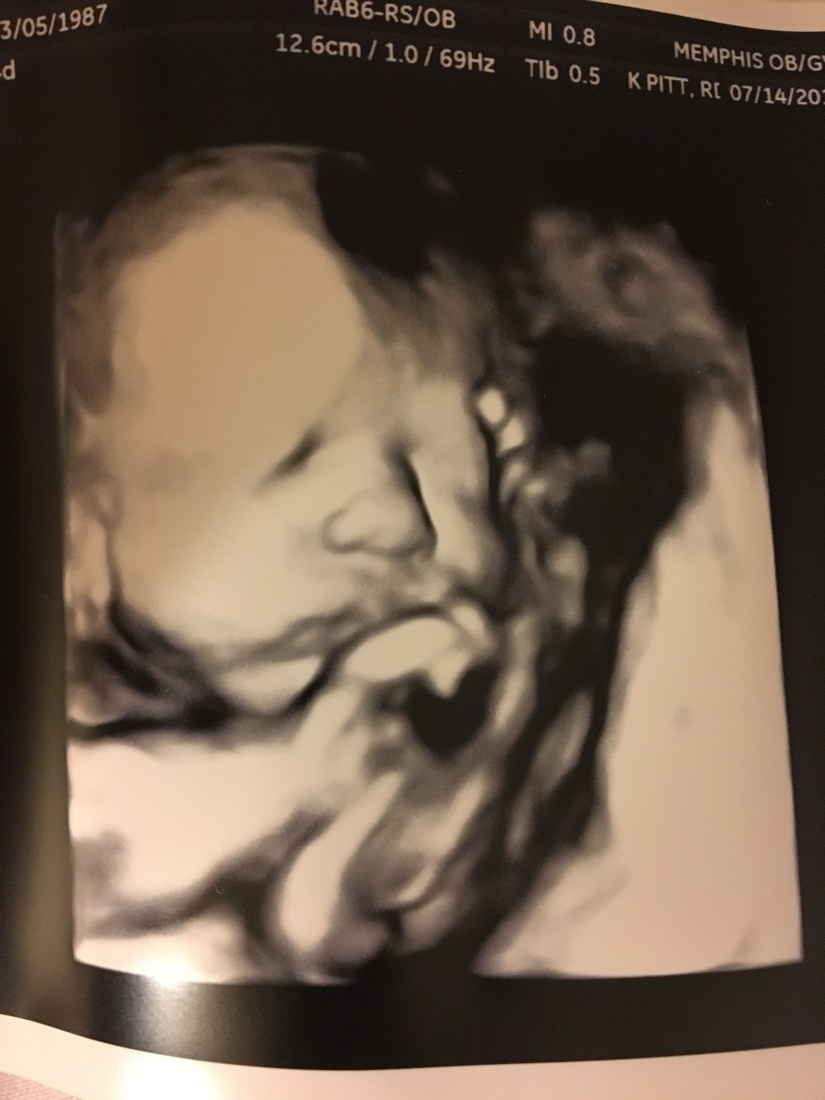

Now- on to the actual doctor appointment update! The fun part! We went today and FINALLY got another ultrasound- the one thing I can thank diabetes for! However, we learned that this dear baby inside of me potentially weighs 6 POUNDS, 3 OUNCES! Um, hello- that is infant- sized for some full-term babies- and this one in me still has 4-5 weeks to go! That is almost HALF of the weight I have gained period from this pregnancy! She also has a longer thigh bone, so she could potentially be a taller baby! Have you met Will and I? Or our families?! None of us are tall…so that’s funny! Her belly is definitely a little rotund as well. She was not a fan of having her picture taken today- but our awesome ultrasound tech- Kelly, was still able to get us some good pictures!

Those are not holes in her head, or weird skin places- she had her face squished up next to the placenta, which makes it hard for the camera to get a good angle to actually show everything!